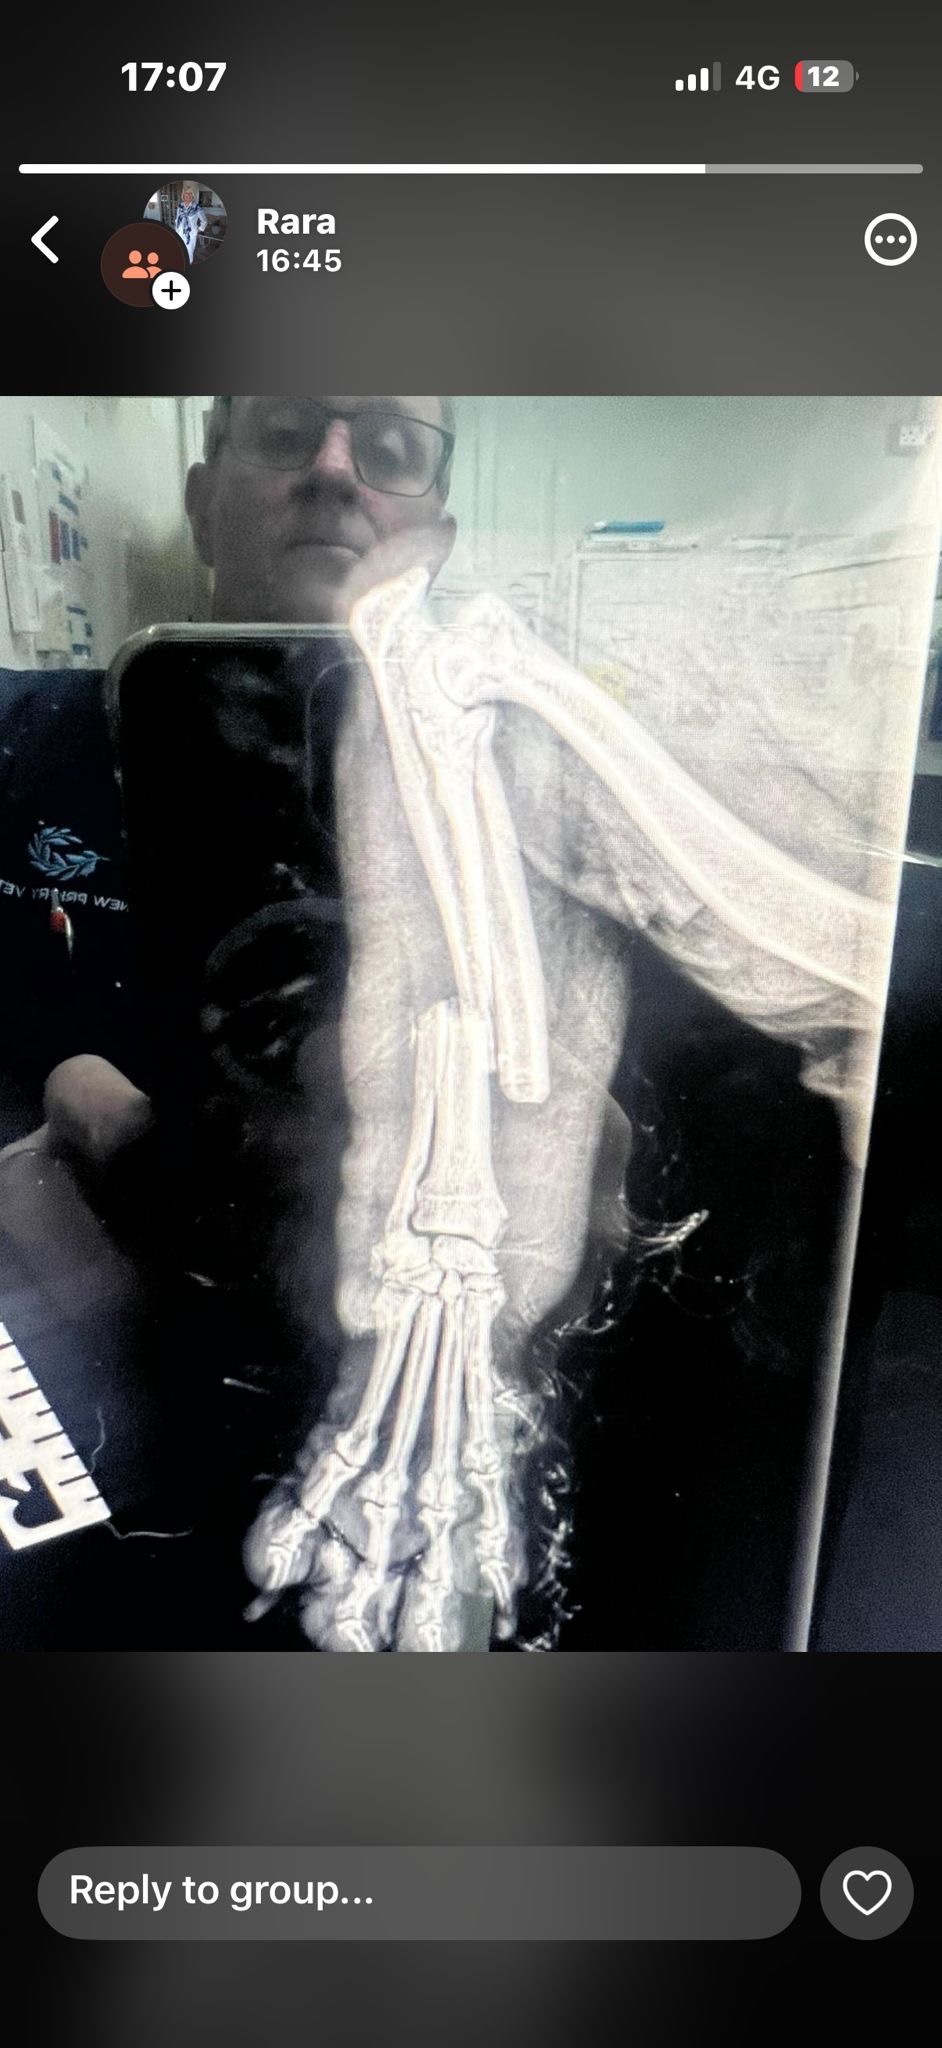

Hi my name is Coral and I’m an eighty year old living with my lovely Cavapoo called Rara. On Friday afternoon she was attacked by two Stafford/Bullie type on a bus in Brighton. She is being cared for at a very caring vets in Brighton but the bill is escalating due to the fact that she is on intravenous medication for pain relief, antibiotics and fluids waiting for an operation to pin and plate her lower front leg that has breaks in her Tibia and Fibula. The operation is scheduled on Wednesday and if there is no infection in the bone from the bit they are hoping to save her leg from amputation. I had pet insurance but the maximum for treatment is £1000 and this will run into many thousands. Any help would be so appreciated.